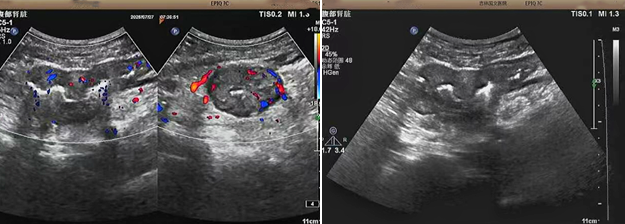

超聲檢查的結(jié)果進一步揭示了病情的細節(jié):下腹部偏左腸壁顯著增厚,原本清晰的層次結(jié)構(gòu)遭到破壞,周圍脂肪間隙變得模糊,網(wǎng)膜回聲也出現(xiàn)增強的現(xiàn)象;同時,腸腔狹窄的情況也得到了確認。經(jīng)過完善的檢查,最終將病變精準定位在乙狀結(jié)腸 - 直腸交界區(qū),并且對病變范圍及周圍浸潤情況做出了評估,這些關(guān)鍵信息為后續(xù)的診療工作提供了重要依據(jù),讓醫(yī)生們能更有針對性地制定治療方案。

我院超聲檢查在此次診療過程中展現(xiàn)出了顯著的技術(shù)亮點。一方面,它能做到 “明察秋毫”,通過高頻探頭可以清晰地顯示腸壁各層結(jié)構(gòu)的變化,為臨床判斷病變性質(zhì)提供了客觀、準確的依據(jù),讓醫(yī)生能更清晰地了解腸道內(nèi)部的病變狀態(tài),另一方面,它實現(xiàn)了 “精準評估”,不僅準確找到了病變的位置,還能全面評估病變對周圍組織的影響,這對于協(xié)助醫(yī)生制定科學(xué)合理的治療方案起到了至關(guān)重要的作用,有助于提高治療的有效性和安全性。